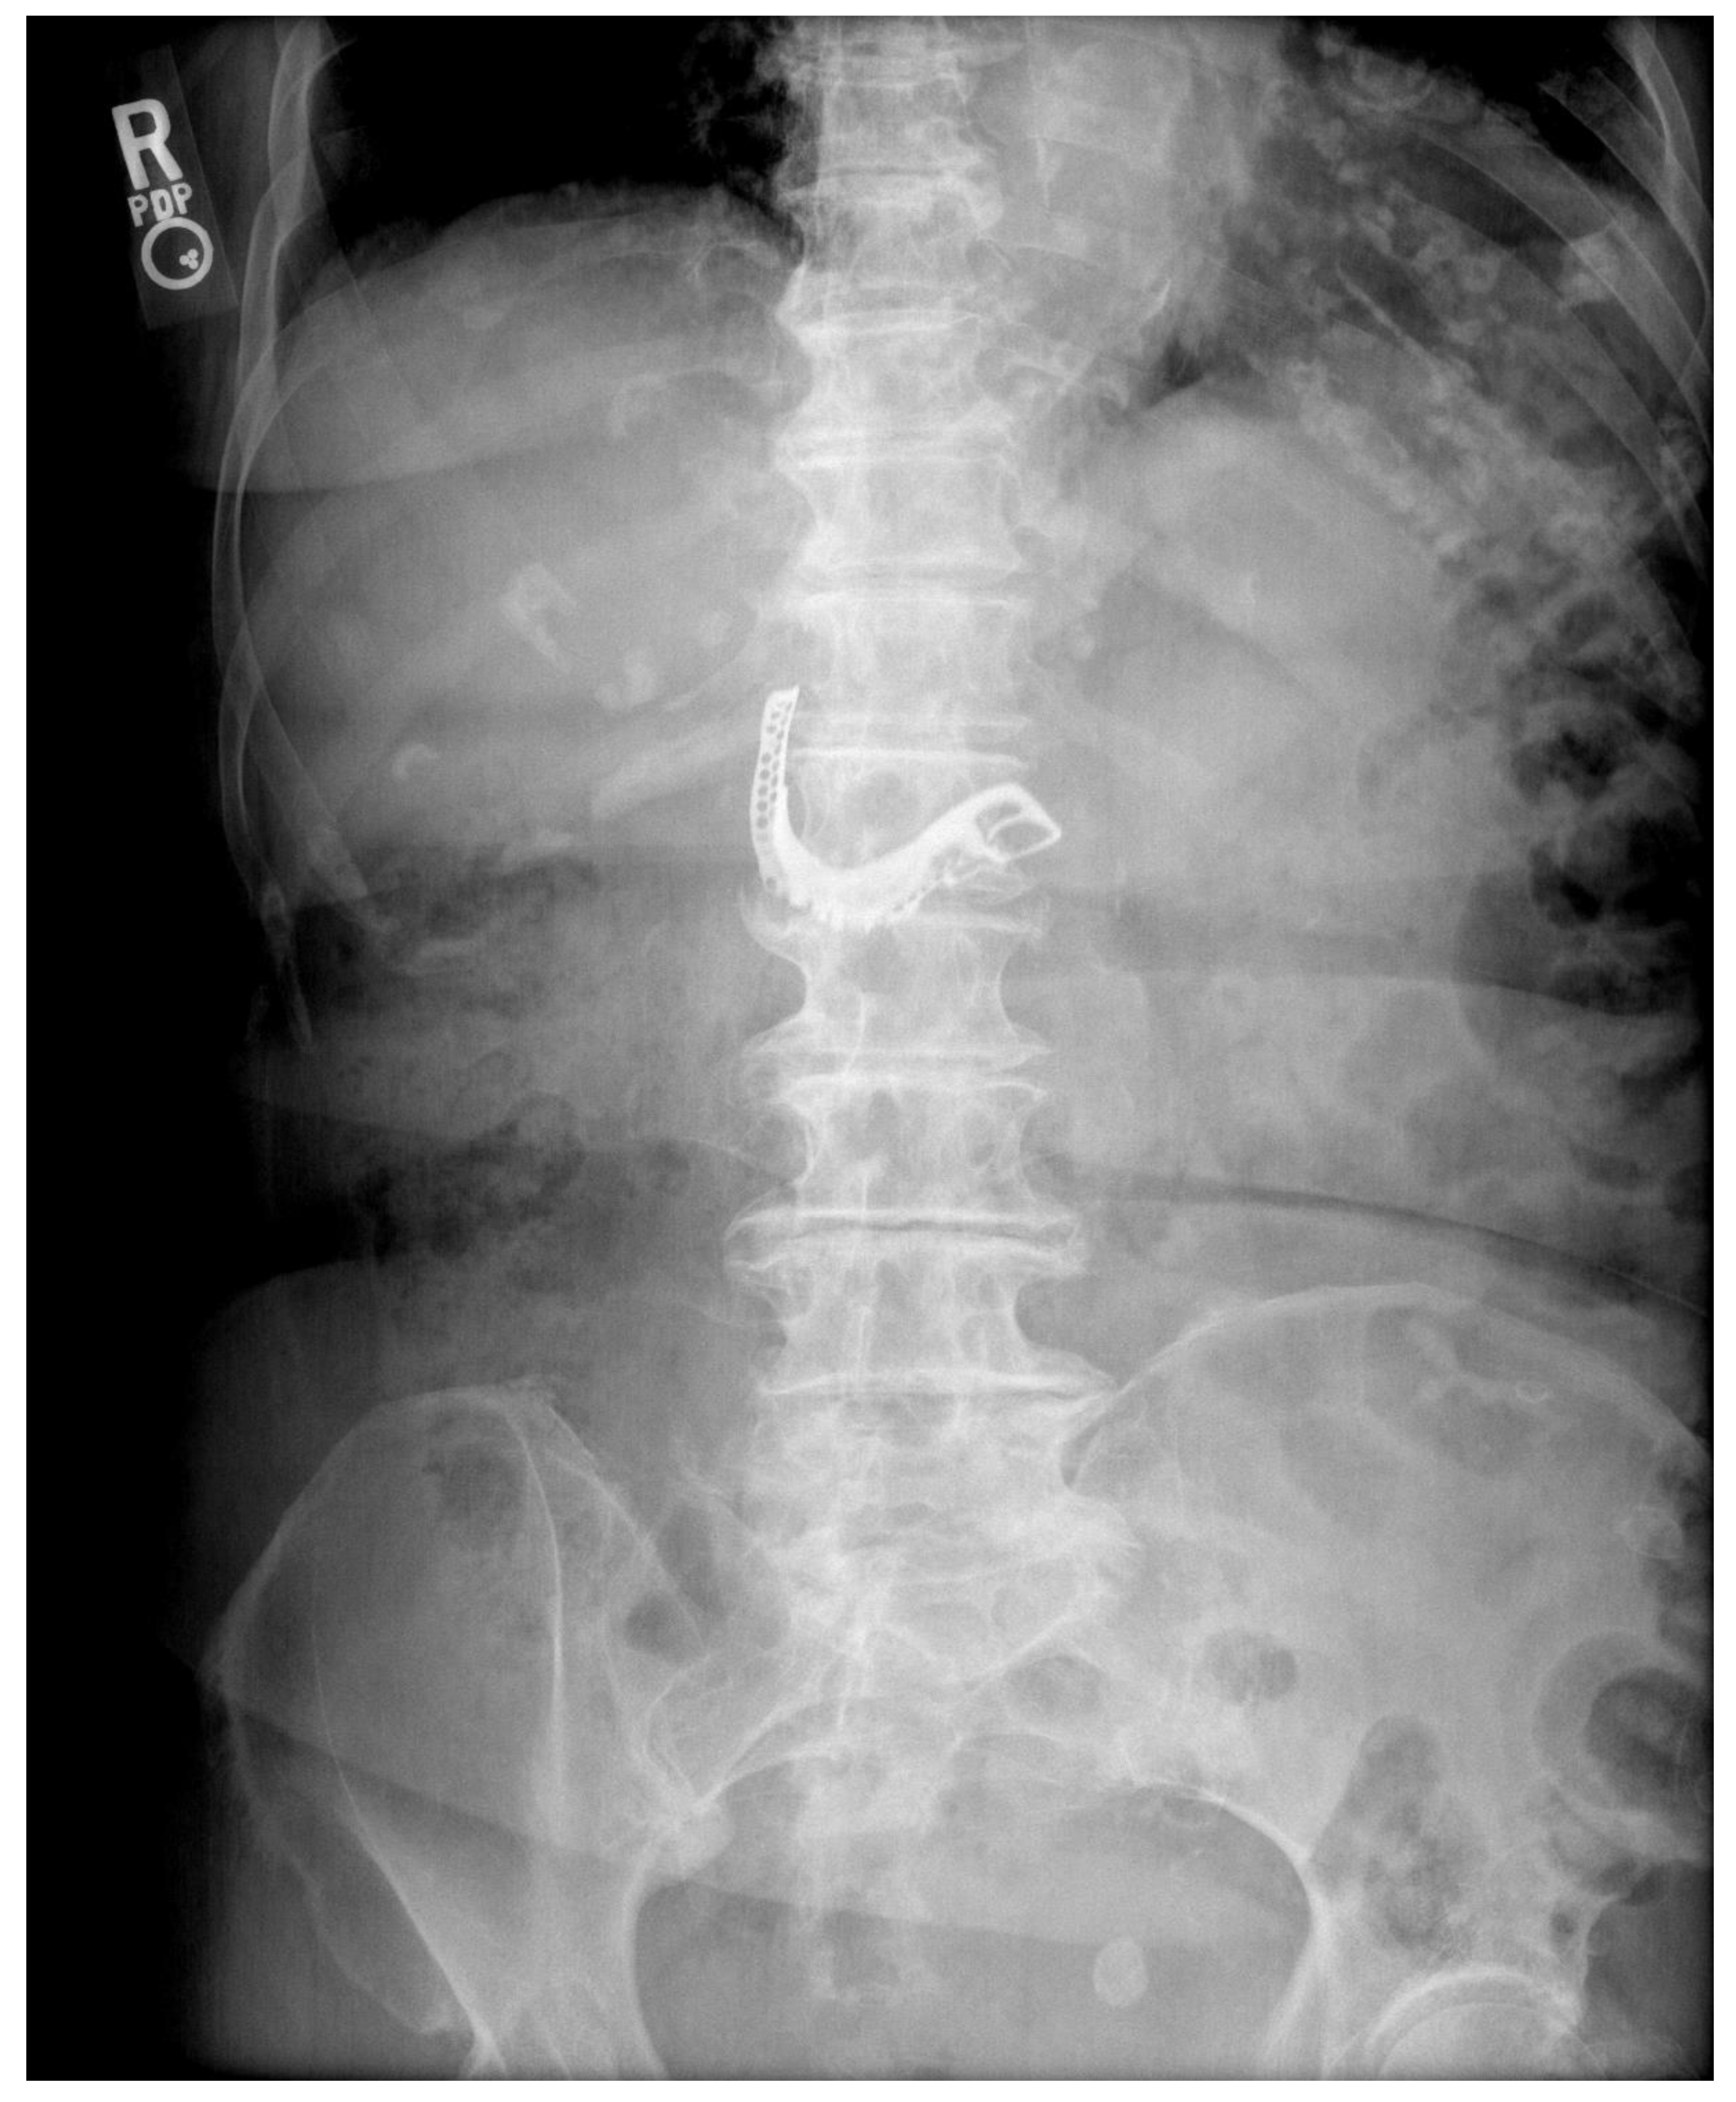

2. Case Report